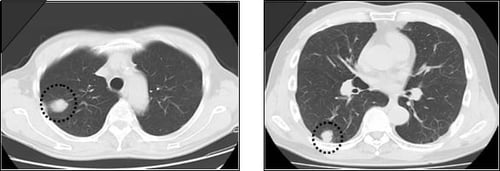

当センターの肺ドックで発見された肺がん

• CT画像

肺がんの知識

肺がんの主な症状は、次のようなものがあります。

咳/痰/血痰/胸痛/発熱/息切れ/声のかすれ

ただし、早期には無症状のことが多いので発見が遅れがちです。